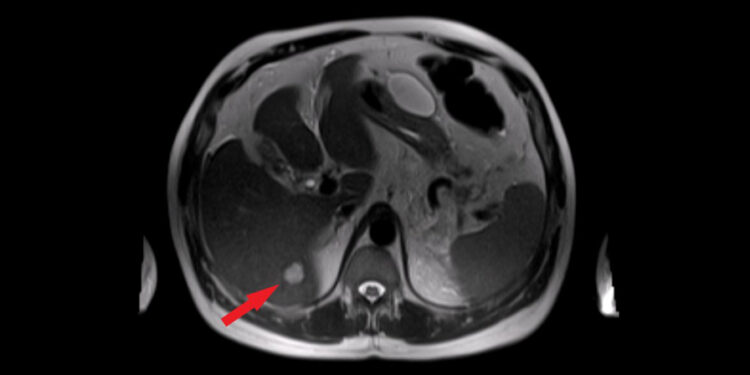

Kaip nustatomos kepenų cistos?

Dažnai kepenų cistos aptinkamos visai netikėtai – darant vidaus organų vizualinius tyrimus dėl kitų priežasčių. Galimi tyrimo metodai:

- Ultragarsinis tyrimas. Gydytojai naudoja aukšto dažnio garso bangas, kad matytų kepenų vaizdą realiu laiku.

- Kompiuterinė tomografija (KT). Naudojant rentgeno spindulius ir kompiuterį sukuriami detalūs kepenų vaizdai trimatėje erdvėje.

- Magnetinio rezonanso tyrimas (MRT). Šio tyrimo metu panaudojamas didelis magnetas bei radijo bangos tam, kad būtų gautas itin aiškus vidaus organų vaizdas.